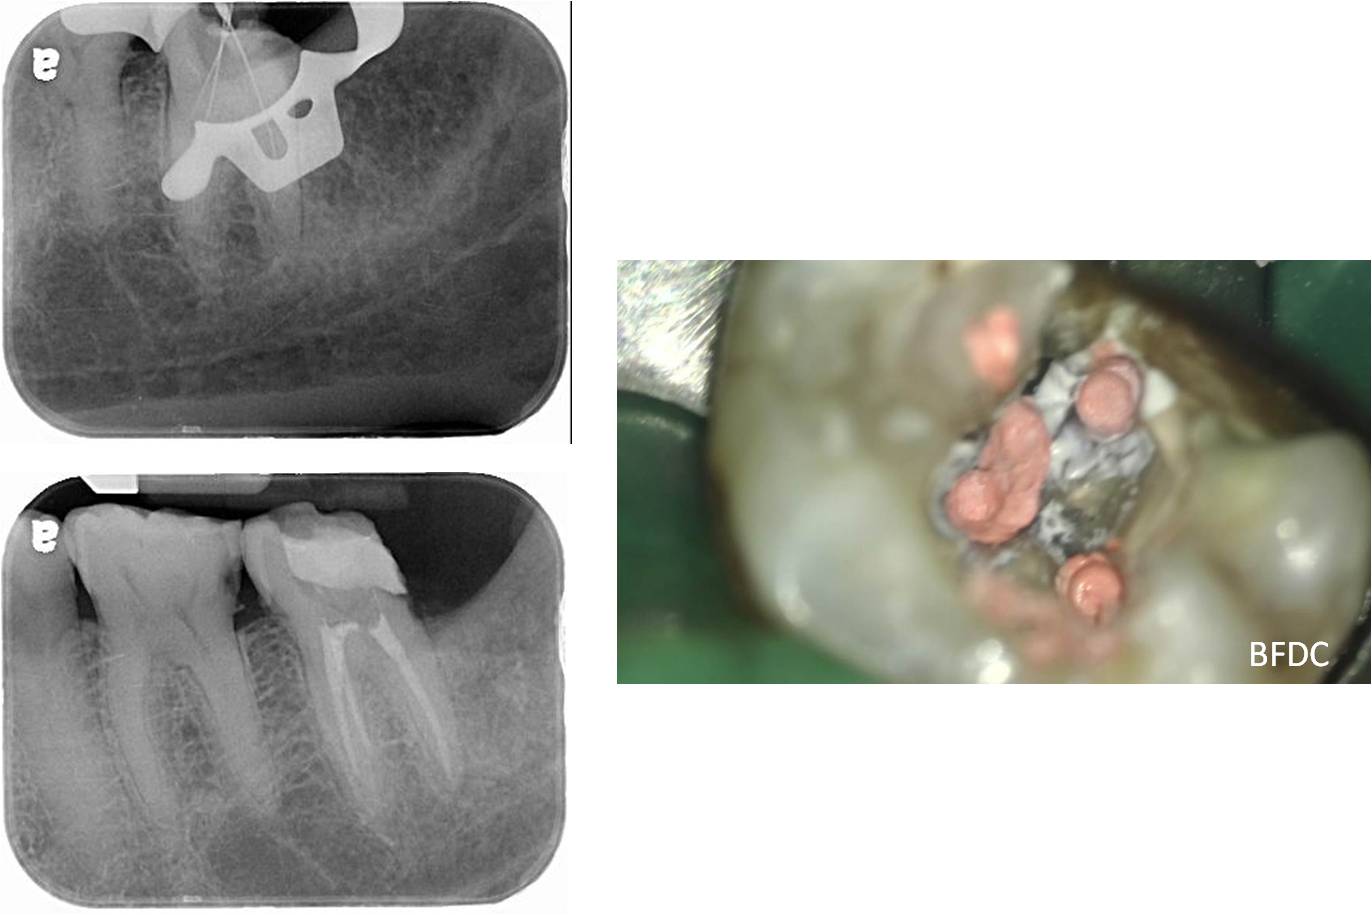

#37-顯微根管治療

冠塊體製備中

上咬合器

陶瓷冠蓋體製作

陶瓷冠塊體